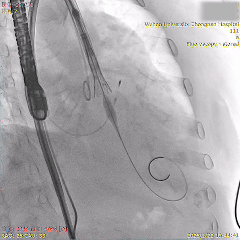

术中影像

瓣膜初始负位定位

第一次瓣膜释放,可见瓣膜轻微向下移动

全展开位评估:左右重合体位造影可见无冠窦侧深度约为瓣下3mm

全展开位评估:左冠切线位造影可见左窦侧深度约为瓣下5mm